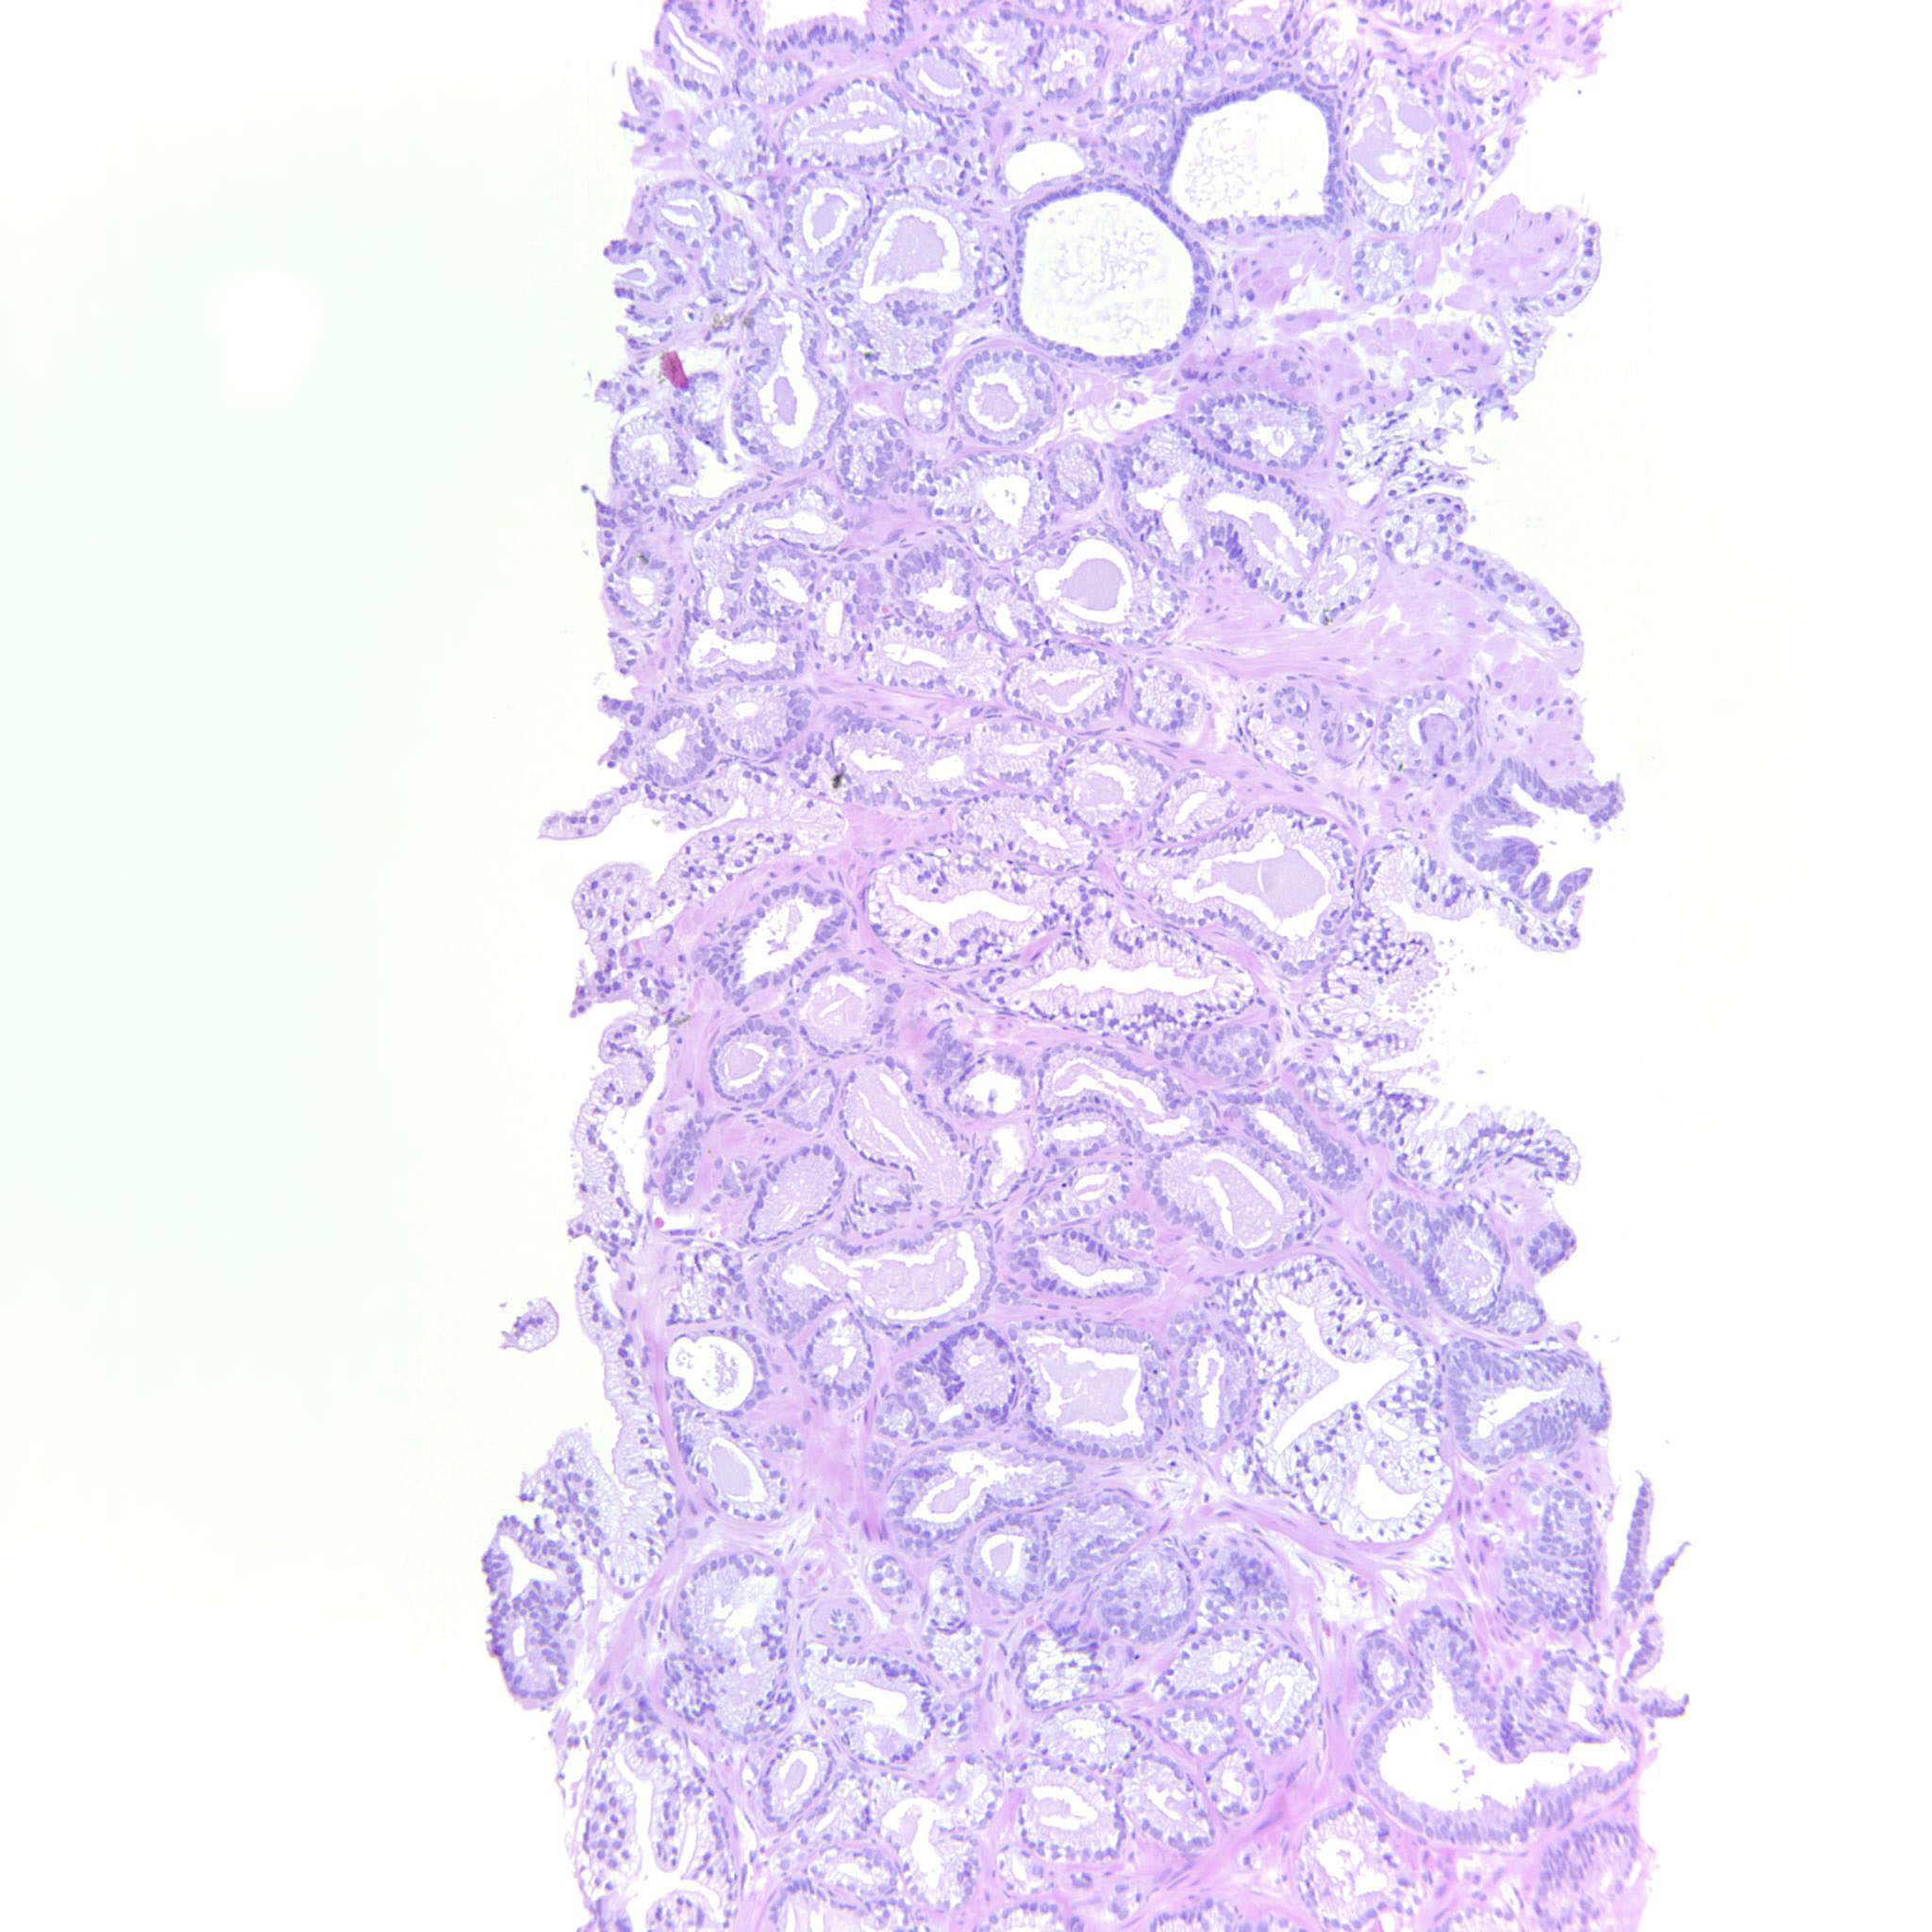

Prostate cancer grading

Case ID: 255